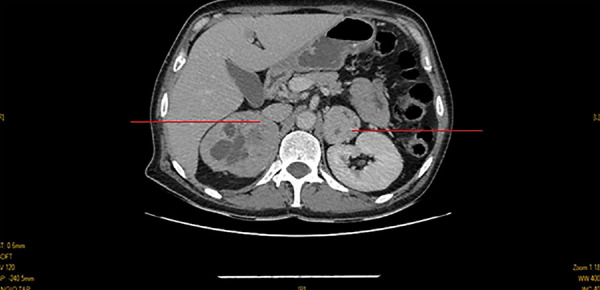

This case report is one of the rare cases of bilateral pheochromocytoma associated with neurofibromatosis type 1. The interest lies in the clinical form in which the diagnosis was revealed. We report the case of a 38-year-old woman admitted for severe hypertension resistant to triple therapy. Clinical examination revealed Cafe-au-lait spots, which are pigmented birthmarks that appear as patches on the skin with a light to dark brown colour. More than six spots are present in an estimated 95% of people diagnosed with neurofibromatosis type 1 (NF1). Abdominal computed tomography (CT) showed bilateral adrenal tumor involvement. The diagnosis of pheochromocytoma was made by measuring urinary Vanillylmandelic acid (VMA). The evolution was favorable after the excision of the tumor, with normalization of blood pressure. In conclusion: resistant hypertension with café au lait spots may indicate pheochromocytoma, especially bilateral, suggesting an underlying genetic condition like NF1, warranting systematic screening.